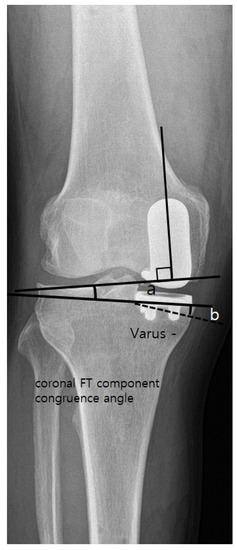

| Coronal femoral component angle (α) (°) | 2.4 ± 4.9 | −1.1 ± 3.2 | <0.001 |

| Coronal FT component congruence angle (°) | 3.4 ± 4.5 | 1.9 ± 2.6 | 0.028 |